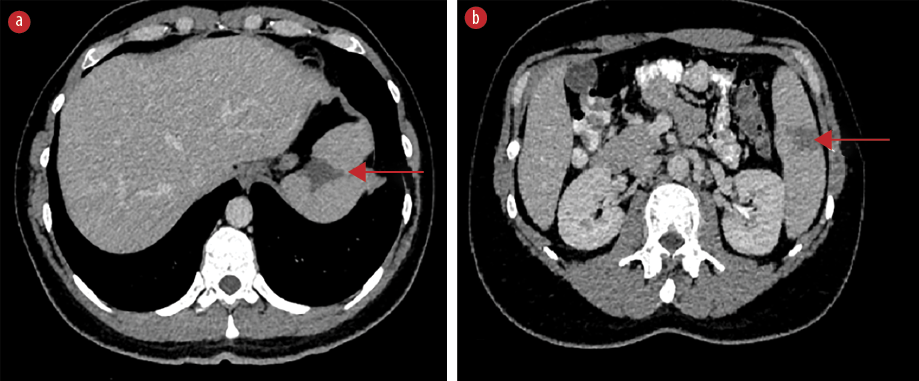

On the fifth day of hospitalization, the patient complained of new-onset left upper quadrant abdominal pain. Clinical examination revealed mild tenderness in the left upper quadrant and a palpable spleen. Computed tomography (CT) of the abdomen with intravenous contrast demonstrated multiple enlarged iliac lymph nodes, hepatomegaly (178 mm in the midclavicular line), and moderate splenomegaly (140 mm in the longitudinal axis). Multiple hypodense splenic lesions were visible without contrast enhancement, suggestive of splenic infarcts [Figures 1 and 2]. CT angiography of the abdomen showed no thrombi in the splenic vasculature. Hypercoagulability workup revealed mildly reduced protein S activity. Molecular testing for inherited thrombophilia (Factor V Leiden, Factor II-prothrombin, Factor XIII, MTHFR, and JAK2 V617 gene mutations) yielded negative results [Table 1]. Transesophageal echocardiography showed no evidence of thrombi, vegetation, or other abnormalities.

Figure 2: Coronal abdominal CT scan with intravenous contrast demonstrating multiple splenic infarcts (red arrows), (a) located at the superior, as well as (b) the middle and lower parts of the spleen.

Abdominal ultrasound is not recommended as the sole imaging modality because of its low sensitivity.6,9,14 The imaging modality of choice is contrast-enhanced CT, on which splenic infarcts commonly appear as wedge-shaped hypodense lesions without post-contrast enhancement after contrast administration.6,7 On magnetic resonance imaging, splenic infarcts are visualized as lesions with low signal intensity on both T1-weighted and T2-weighted images.9 In the present case, abnormal lesions suggestive of infarcts became evident on CT scan with intravenous contrast as wedge-shaped lesions without contrast enhancement.